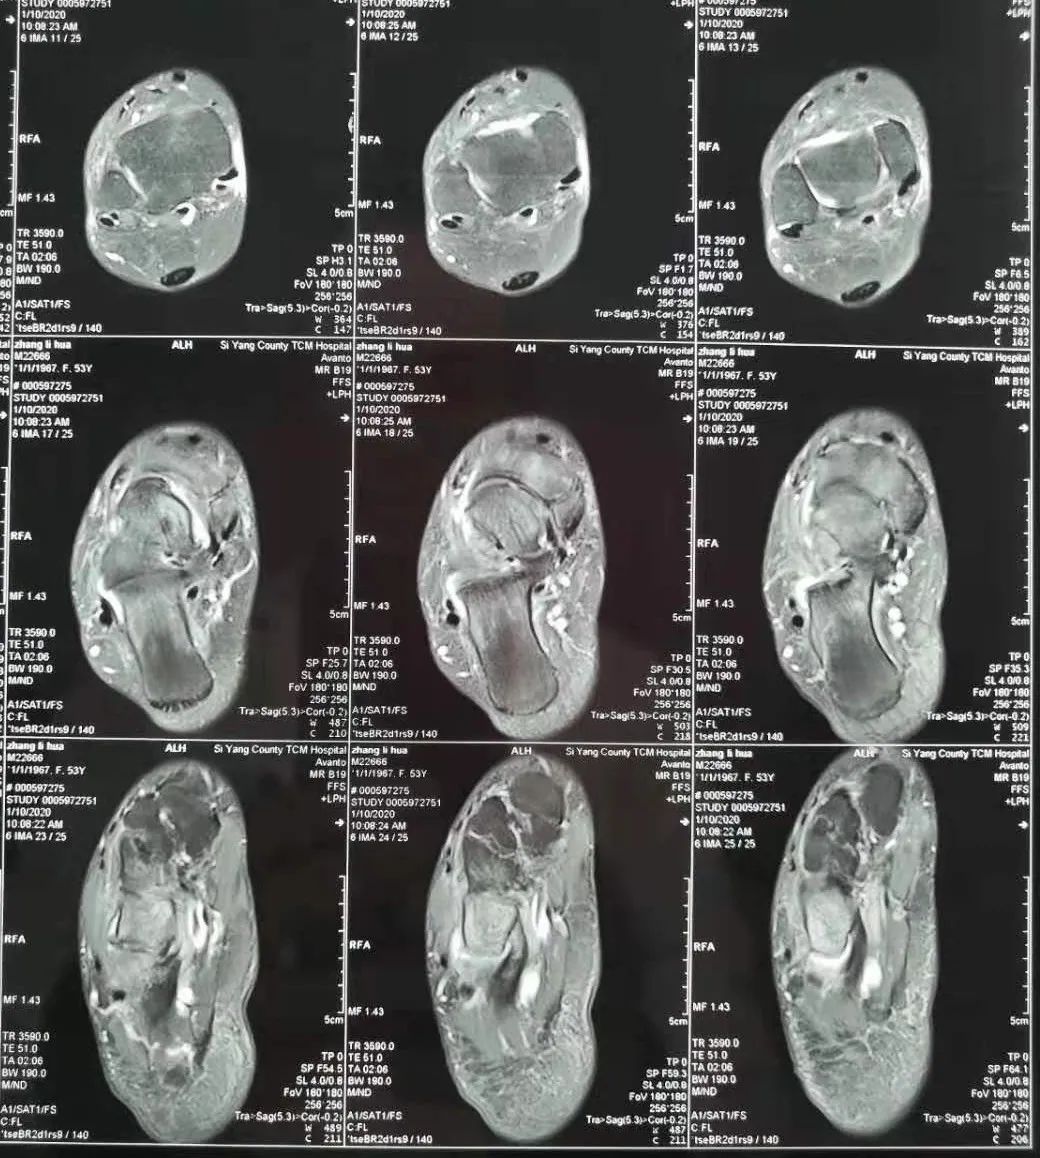

图为术前MRI:软骨下骨骨髓水肿,关节腔周围少量积液,外侧腓骨前韧带高信号